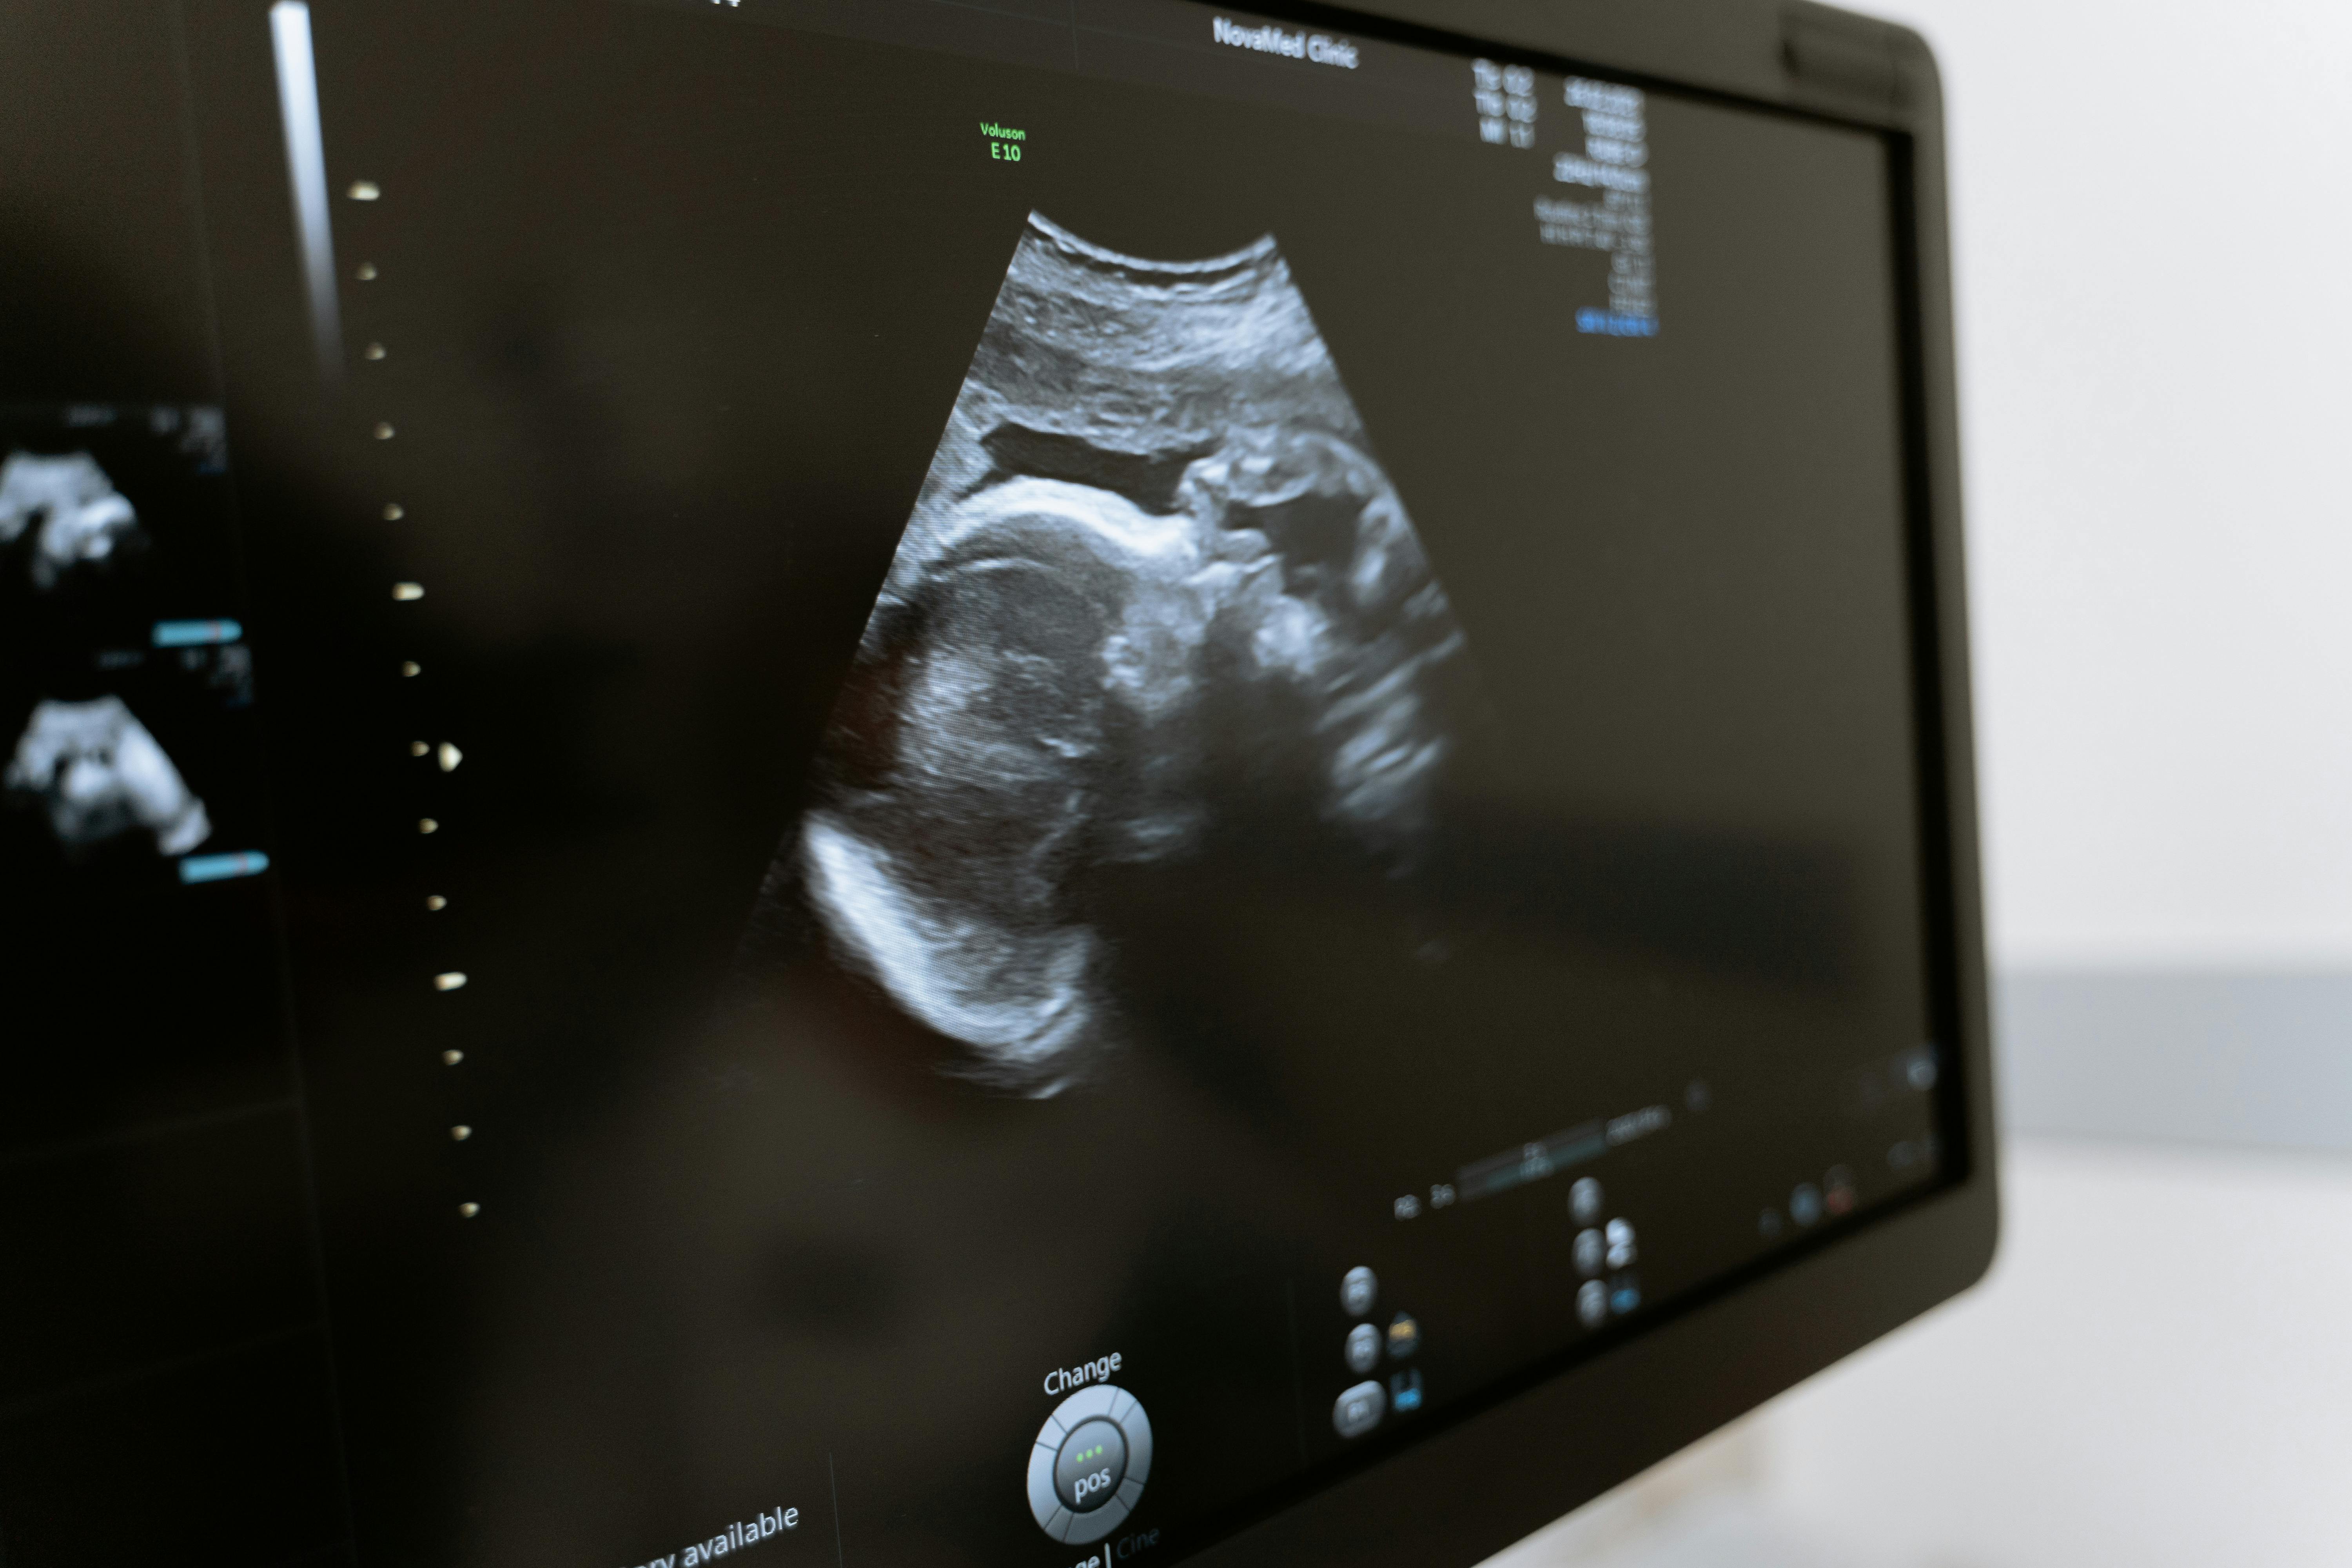

임신을 하면 꼭 챙겨야 할 영양제들이 있습니다. 시기별로 어떤 영양제를 먹어야 할지 알고 먹어야 효과가 있습니다.

시기별로 섭취해야 할 영양제와 복용법을 알아보겠습니다.